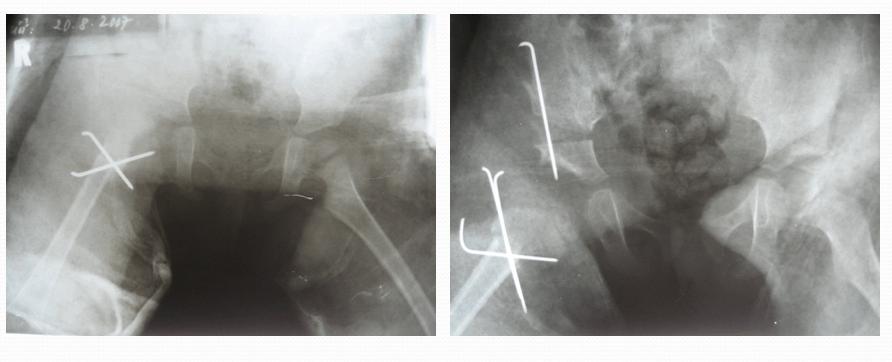

Phẫu thuật

6 tháng đến 2 tuổi. Nếu kỹ thuật nắn chỉnh không thành công, cần phải phẫu thuật mở để đưa chỏm xương đùi vào ổ khớp. Sau đó, trẻ được bó bột spica để duy trì vị trí hông thích hợp.

Sau phẫu thuật trẻ cần được bó bột cố định một thời gian 2 -3 tháng, tập phục hồi chức năng để lấy lại tầm vận động, cơ lực hai chân và khả năng đứng, đi lại.

Cần đánh giá lại trẻ định kỳ qua khám lâm sàng và chụp X quang/CT hoặc cộng hưởng từ.

Bó bột sau phẫu thuật